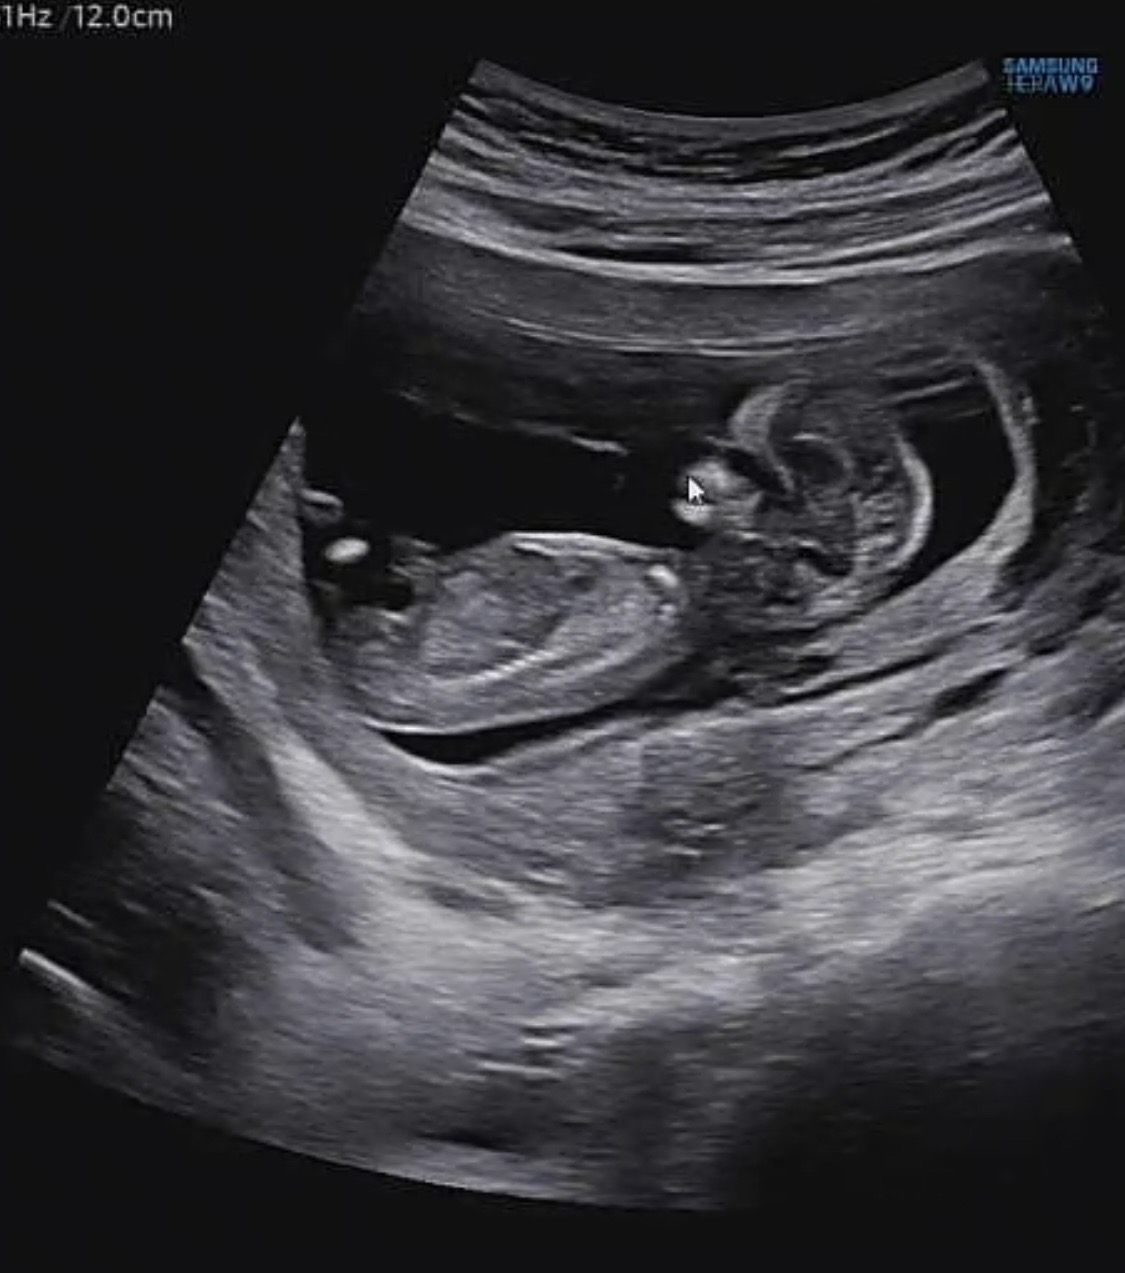

의사선생님께서 자꾸 다리사이에 모가 보인다고 하시는데.. 12준데 벌써 보이나요..... 🥹